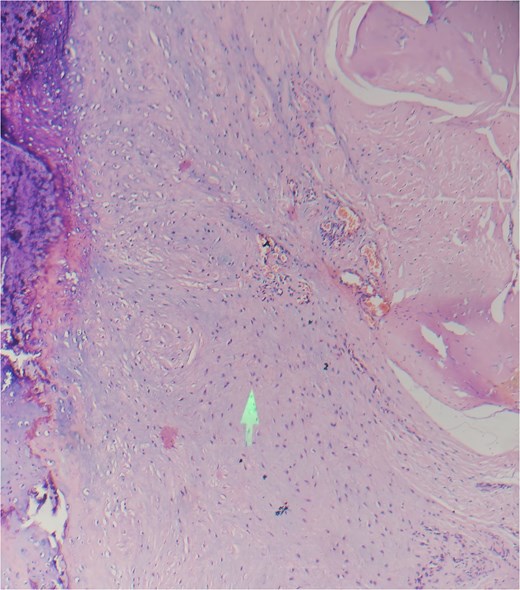

Guided biopsy was taken and sent for histopathological examination but was inconclusive. A chondroblastoma diagnosis was taken into consideration as per radiological imaging, and the tumor was removed, and the great toe was disarticulated. The incision was marked and deepened in layers. Flaps were raised and friable, gritty, and decalcified bone was identified, and hence disarticulation of the left great toe was done (Fig. 3) and sent for histopathological examination. The postoperative course was uneventful. The patient was discharged on postoperative day (POD) 2 with sutures in situ. The patient came for follow-up after 10 days, and the suture line was found to be healthy with no active discharge or signs of inflammation and no restriction of movements. Sutures were removed on POD-10. Under a microscope, hematoxylin and eosin (low power mode) section shows immature chondrocytes (chondroblasts) round in shape with scanty cytoplasm, round nuclei with prominent nucleoli arranged into lobules separated by thin fibrous septae, and enclosed within a capsule suggestive of chondroblastoma (Fig. 4).